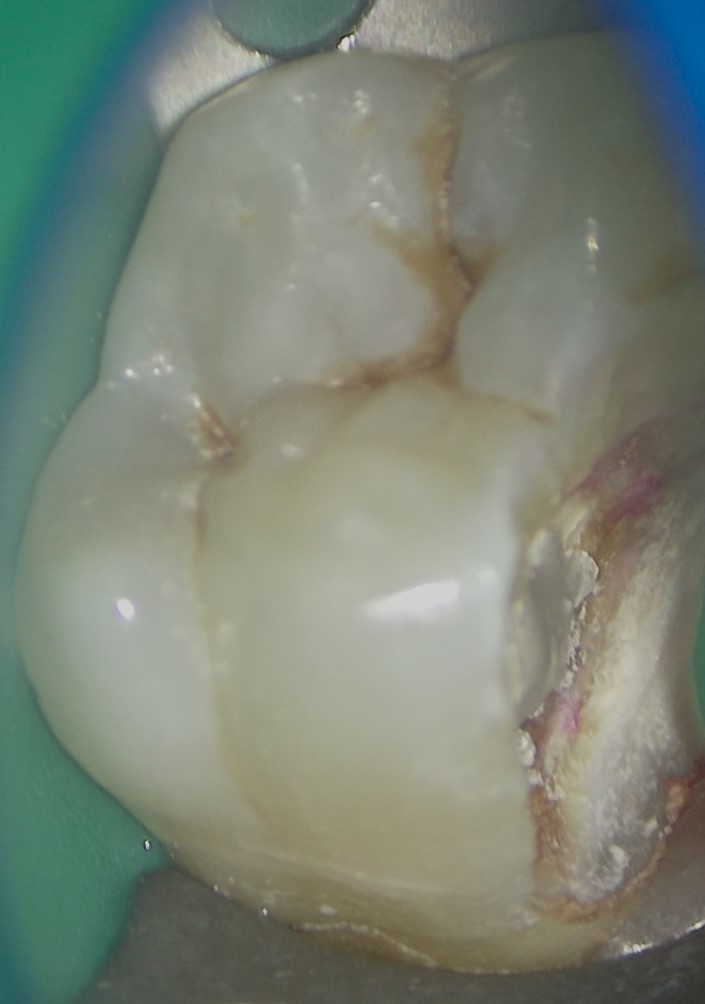

虫歯除去前

虫歯除去中かなり大きく深い虫歯 ラバーダム防湿し、